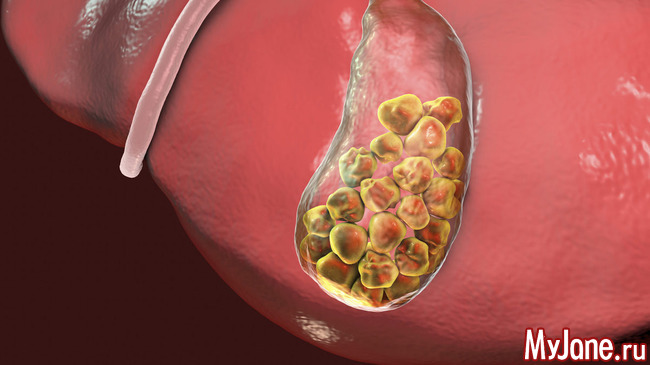

Анатомия и особенности Гартманова кармана желчного пузыря